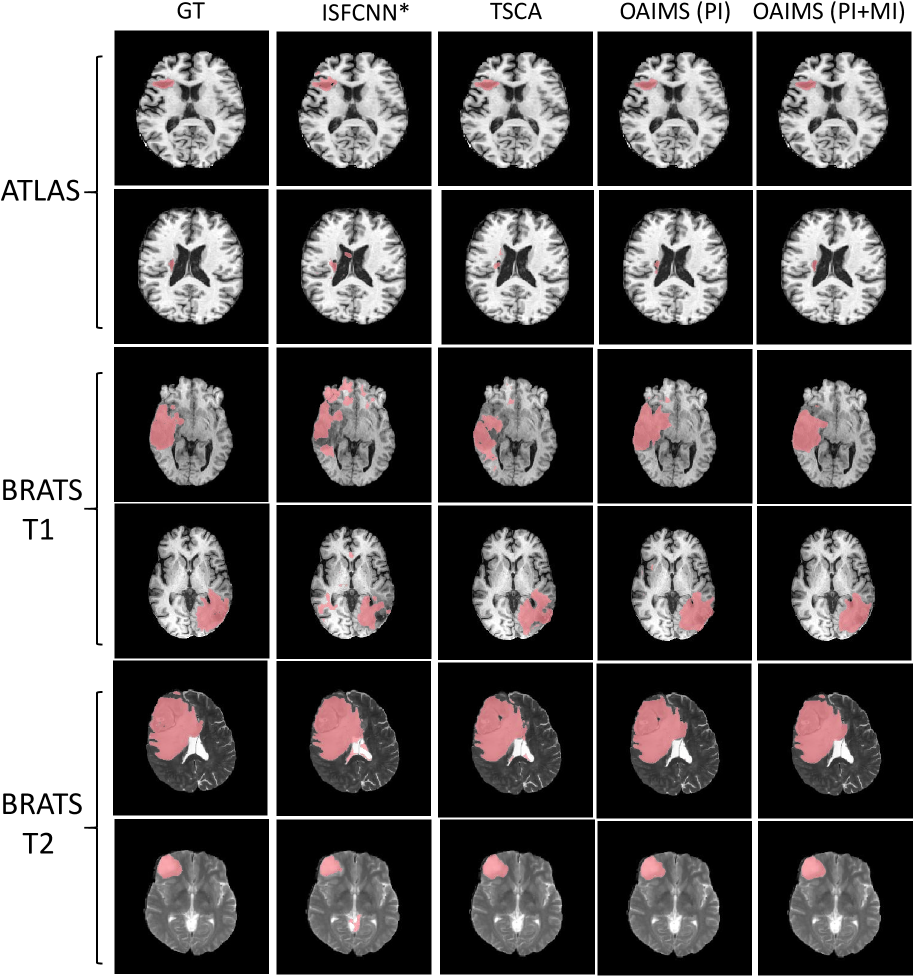

Fig. 3 presents the visualization results demonstrating the adaptation performance on the BRATS dataset. The segmentation map is overlaid in red on the original image. Our OAIMS (PI+MI) method produces segmentations that are closest to the ground truth (GT), with more accurate boundaries compared to other methods.

Figure 3: Visualizations on BRATS Databases demonstrating adaptation to different modalities and pathologies (Trained on BRATS Flair for BRATS T1 and BRATS T2, Trained on BRATS Flair/T1/T1c for ATLAS